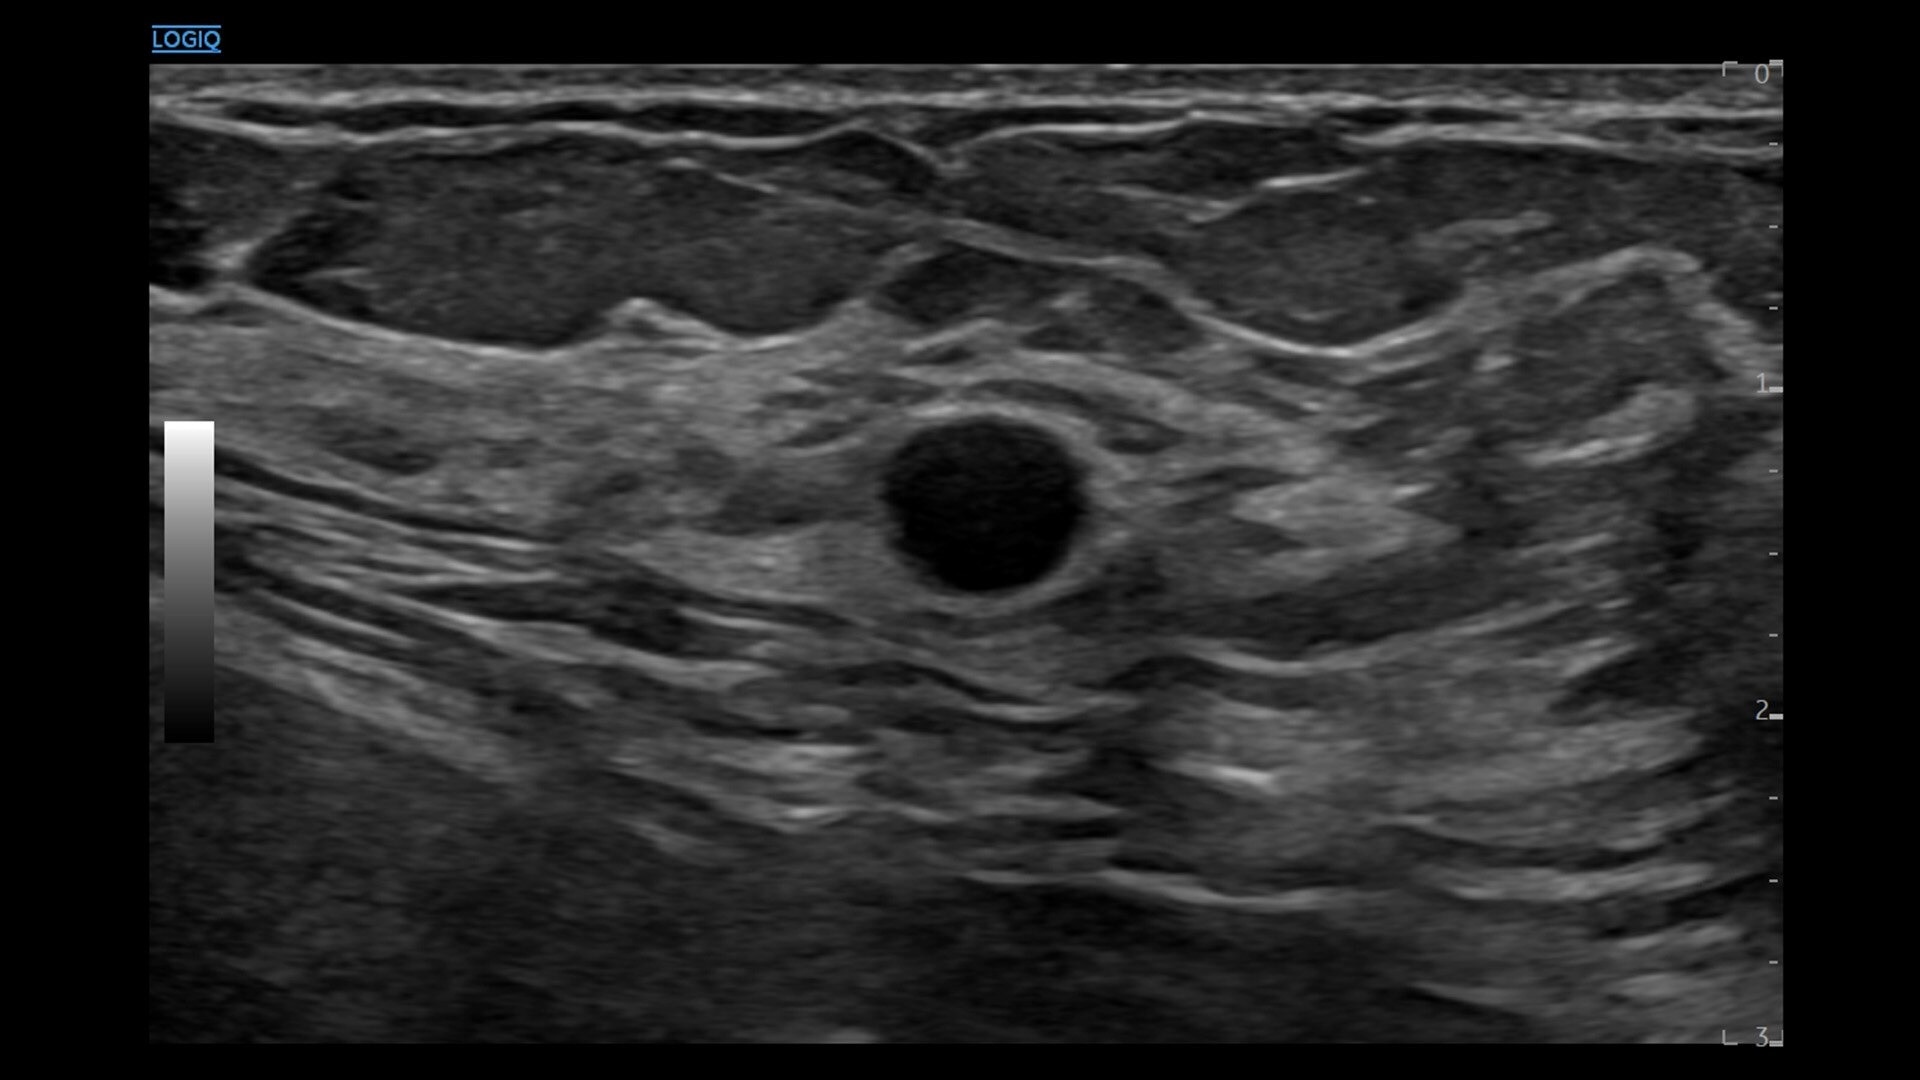

• cSound™ Architecture delivers exceptional clarity and resolution from near field to depth—with all pixels in focus

• Advanced flow modes give you the flexibility, from large vessels to fine microvascular detail, to visualize blood flow with precision

• 2D shear wave elastography with quality map provides quantitative insight into tissue elasticity—helping you assess different structures with confidence